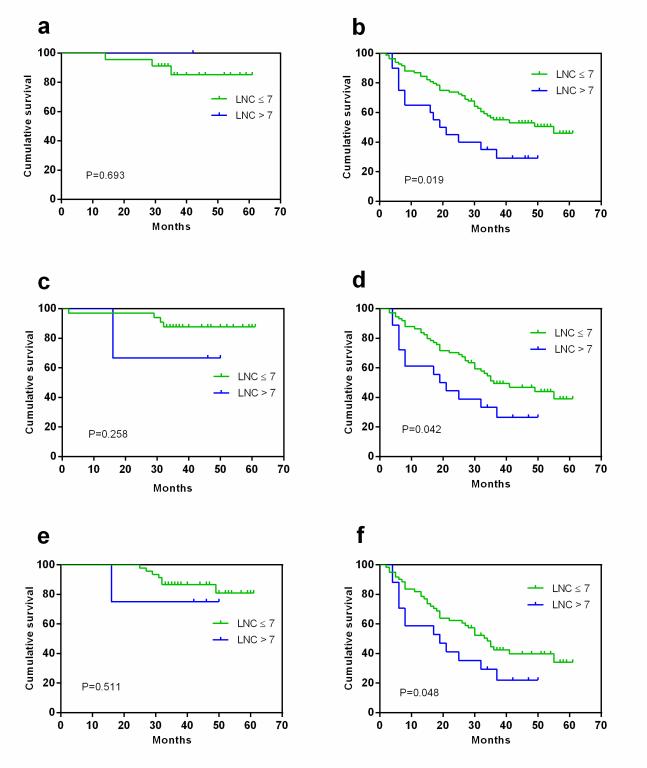

MDCT 淋巴结数目对胃腺癌切除术后的总体生存的影响依据计数标准及 TNM分期不同而不同���。对于 T1-2 的胃癌患者���,预后的评估更应警惕 8mm 以上的 MDCT淋巴结数目���。而对于相对进展期的 T3-4, N+, 与 III 期的胃癌患者��,推荐较小的大小(5mm)作为标准以 MDCT 淋巴结数目对胃癌患者进行预后评估����。

图4 依据TNM分期��,MDCT淋巴结数目对胃癌患者总体生存的影响(5mm为阈值)